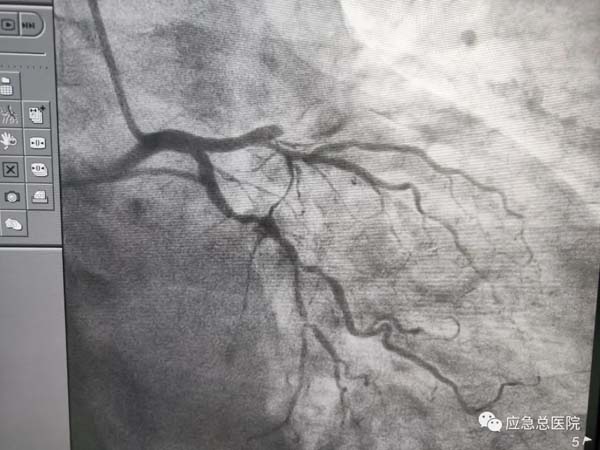

手术前

生命在接力。来到应急总医院后,为患者第一时间进行造影检查,结果提示:三支病变,前降支近端100%闭塞,也就是说供应心脏的三条血管均有严重的狭窄,而最主要的血管——前降支已经完全堵死,晚一点救治后果不堪设想。吴迪教授第一时间研判:务必马上开通闭塞血管,一刻都不能耽搁!因为应急总医院有一支经验丰富的介入团队,在吴迪教授的指导下,在范煜东副主任的熟练操作下,在张子龙副主任医师、张庆军主治医师及导管室护士、技师的通力配合下,病人的闭塞血管及时开通,如久旱甘霖般将鲜活的血液重新给濒临坏死的心肌细胞。手术一做完,病人就长舒一口气:“不疼了!舒服了!”在手术室门口焦急守候的家属,此刻喜极而泣。看看时间,从张大爷到光熙医院就诊,再转运到应急医院完成手术,仅用了50分钟。